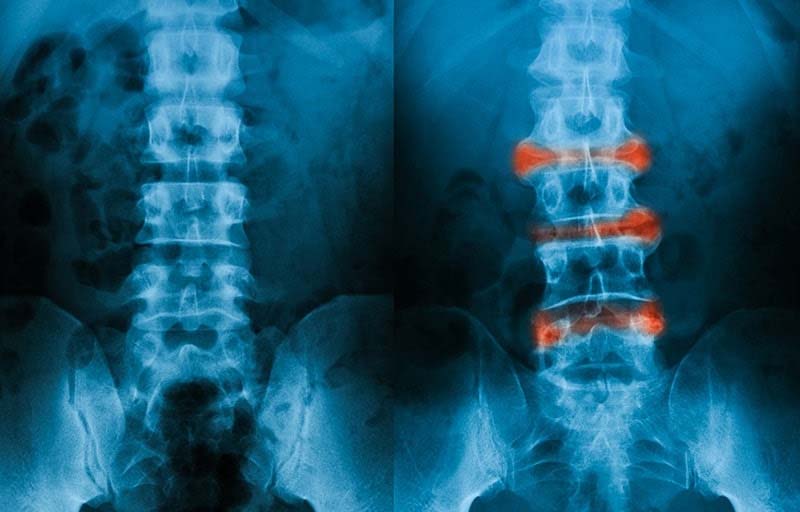

Hội chứng thắt lưng hông, còn được gọi là hội chứng rễ thần kinh thắt lưng cùng, là một tình trạng bệnh lý phát sinh khi các cấu trúc tại cột sống thắt lưng bị tổn thương. Những tổn thương này dẫn đến chèn ép hoặc kích thích các rễ thần kinh tủy sống từ L1 đến L5, gây ra các triệu chứng lâm sàng đặc trưng. Về bản chất, hội chứng thắt lưng hông là tổn thương kết hợp bởi 2 hội chứng nhỏ là hội chứng cột sống và hội chứng rễ thần kinh.

Thoát vị đĩa đệm là nguyên nhân hàng đầu gây ra hội chứng thắt lưng hông, đặc biệt là tình trạng đau thần kinh tọa. Cơ chế bệnh sinh xảy ra khi nhân nhầy đĩa đệm thoát ra khỏi vị trí bình thường do bao xơ bị rách. Khối thoát vị này sau đó chèn ép trực tiếp lên các rễ thần kinh tủy sống đi ra từ cột sống, dẫn đến các triệu chứng lâm sàng đặc trưng như đau dữ dội và các dấu hiệu tê bì, yếu cơ ở chi dưới.

- Thoái hóa khớp cột sống: Đây là một bệnh lý mạn tính do quá trình lão hóa tự nhiên, đặc trưng bởi sự bào mòn sụn khớp, tổn thương xương dưới sụn và hình thành các gai xương. Những thay đổi thoái hóa này có thể dẫn đến hẹp ống sống hoặc hẹp lỗ liên hợp, từ đó gây chèn ép các rễ thần kinh, dẫn đến đau và các triệu chứng thần kinh khác.